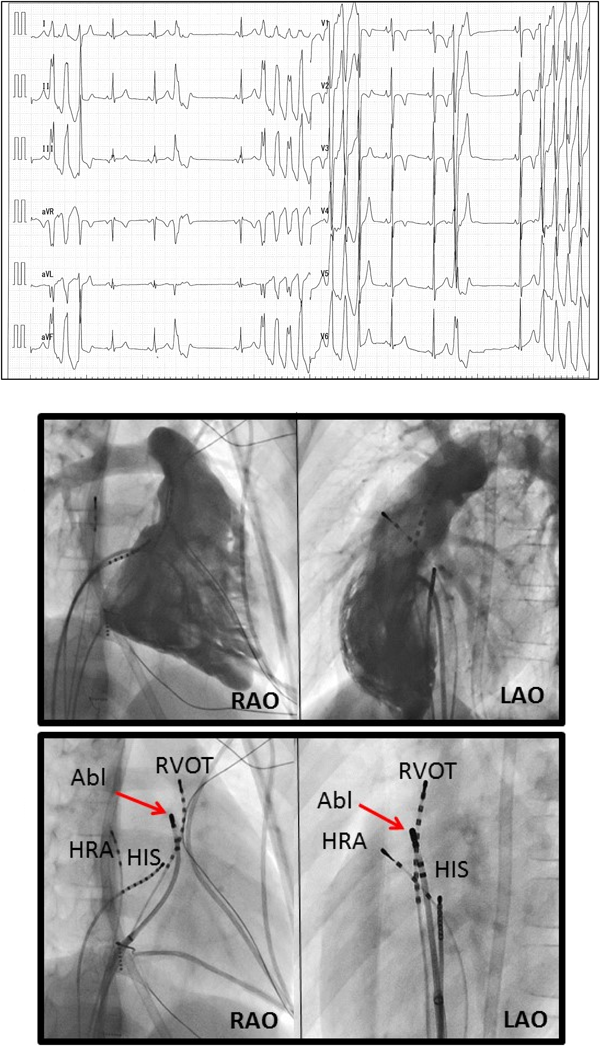

良性心室期外収縮として長期経過観察中に発症した特発性多形性右室流出路起源心室頻拍の1男児例Idiopathic Polymorphic Right Ventricular Outflow Tachycardia Developed after a Long-term Follow-up of Benign Premature Ventricular Contractions with a Normal Structural Heart